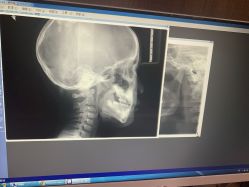

• 睿宝儿科·眼科·口腔(静安大悦城门诊部)

• -睿宝儿科·眼科·口腔(静安大悦城门诊部)

相册

kickgirl 上传于 20-07-17 | 报错